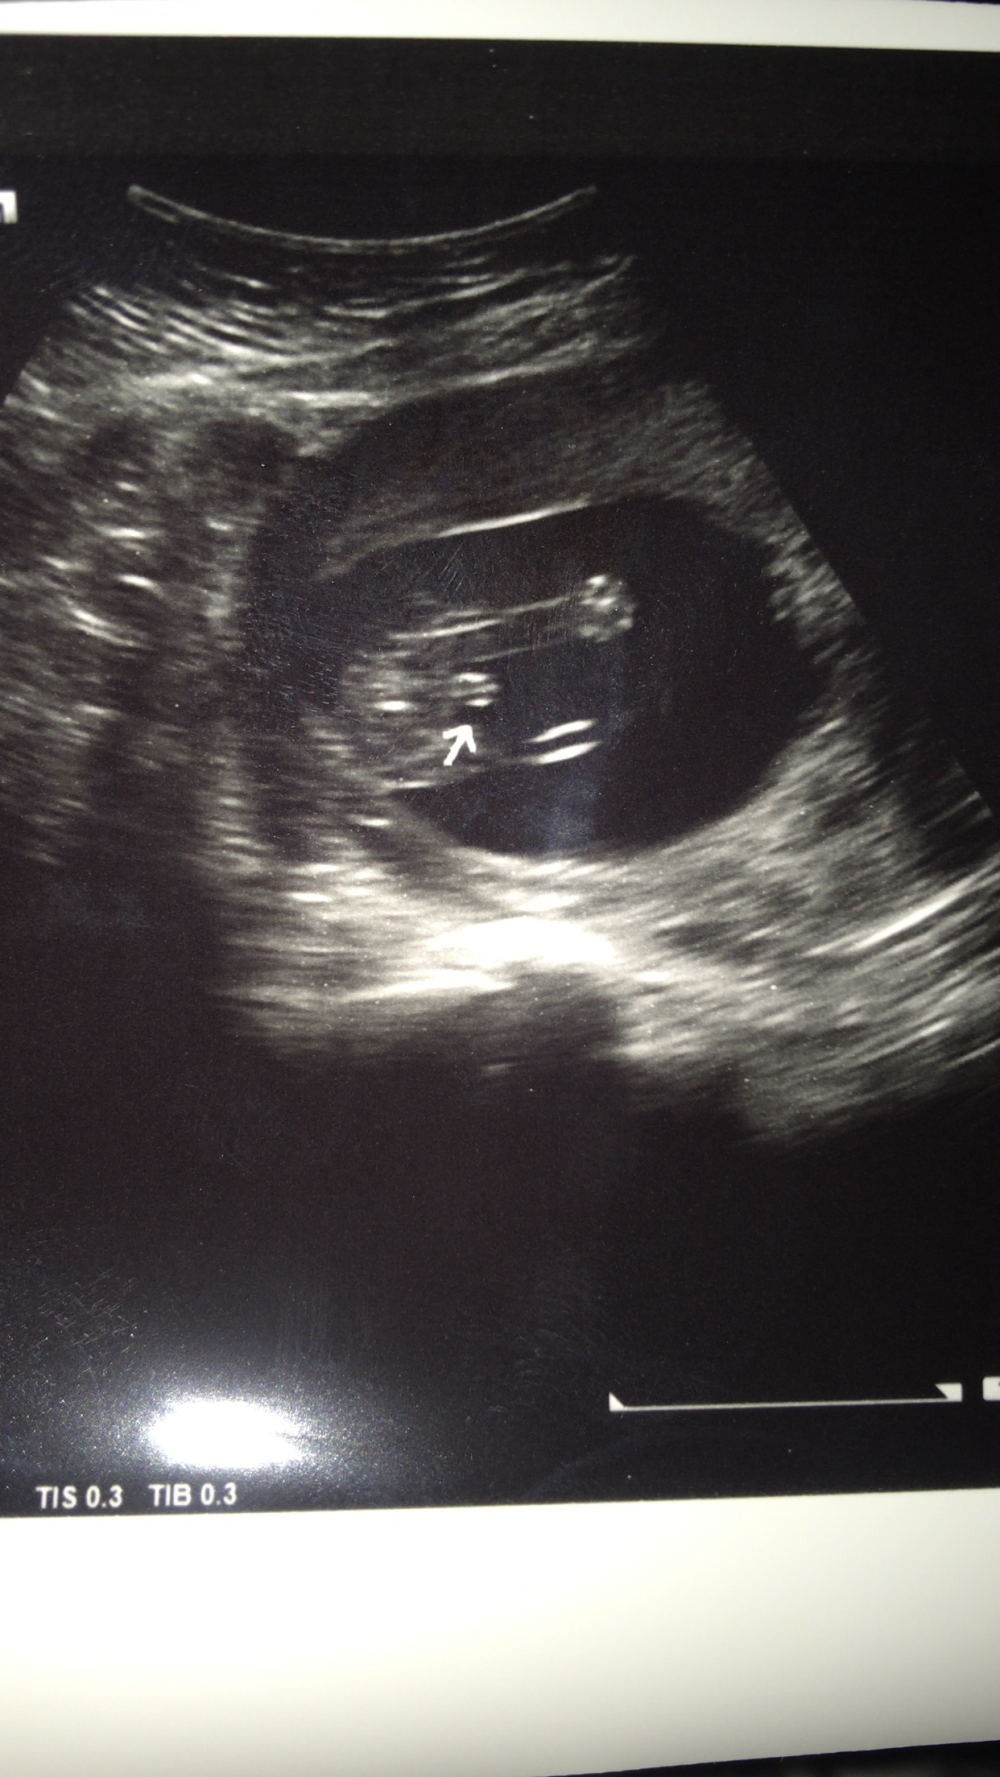

قبل اسبوع عملت سونار والدكتورة قالت لي ٦٠٪؜ بنت طبعاً كان لي ١٦ اسبوع واعطتني موعد بعد اسبوع

اللي هو اليوم اول ما حطت الجهاز على بطني قالت ولد

هذي صورة السونار

مبين انه ولد والعلم عند الله

ولد